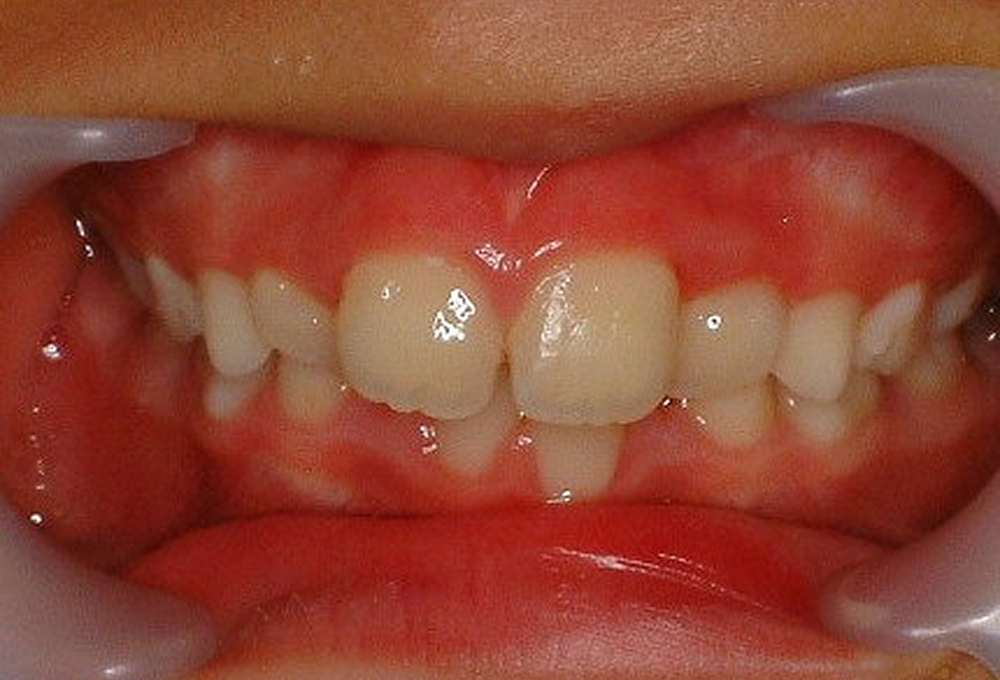

①術前:8歳 4前歯が反対咬合で歯が並ぶスペースも不足

②拡大床(エキスパンジョンスクリュー 床矯正装置)を作製

③装着した所

④4ヵ月後 反対咬合が改善し、歯が並ぶスペースも確保できた。ここまできていれば永久歯列になったときの矯正は簡単です